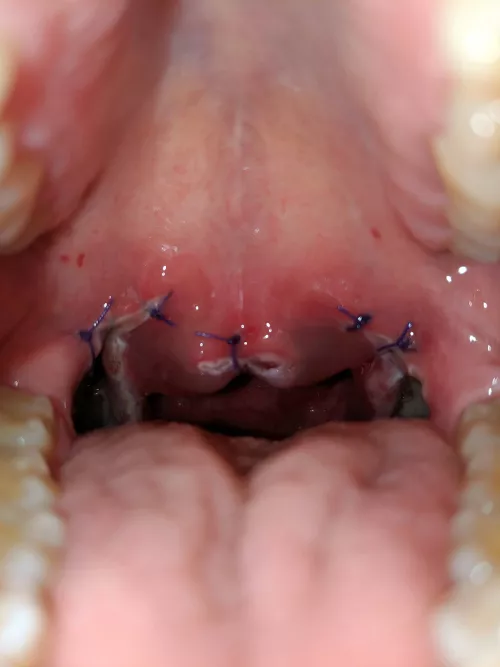

Popped a pimple on my lip and now it looks like this nudes